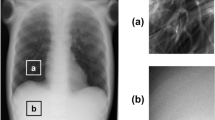

In this work we employ computer-vision techniques to detect natural biological symmetries in breast MR scans. Currently, breast MR images are assessed in terms of the kinetics and location of uptake of Gd-DTPA. However, mammographic interpretation often uses symmetry between left and right breasts to indicate the site of potential tumour masses but has not been used in breast MRI. In this study, we present such a method for characterizing breast symmetry based on three objective measures of similarity including multiresolution non-orthogonal wavelet representation, three-dimensional intensity distributions and co-occurrence matrices. Statistical feature distributions that are invariant to feature localization are computed for each of the similarity metrics. These distributions are later compared against each other to account for perceptual similarity. Studies based on 51 normal MRI scans of randomly selected patients showed that the sensitivity of symmetry detection rate approached 94%. The symmetry analysis procedure presented in this paper can be applied as an aid in detecting breast tissue changes arising from disease.